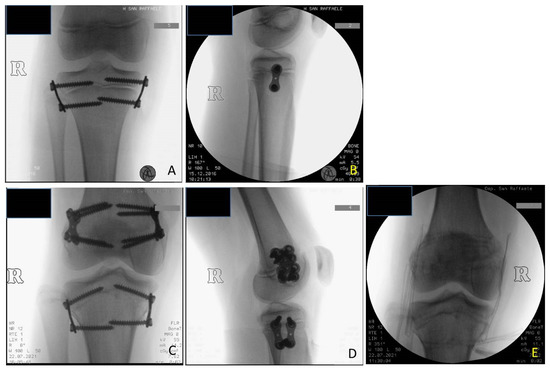

Figure 6. BWS (Beckwith-Wiedemann syndrome) female patient with LLD (leg length discrepancy) right: (A) at age of 9.8 years PTE (temporary proximal tibia epiphysiodesis) was performed using 8-plates; X-ray in anteroposterior projection (B) X-ray in lateral projection; (C) at age of 10.7 years DFE (distal femur epiphysiodesis) was performed using quad-plates, X-ray in antero-posterior projection; (D) X-ray in lateral projection; (E) at age of 14.3 years removal of hardware by absent LLD, X-ray in antero-posterior projection showing closed physis. (8-plateR and quad-plateR; Eight Plate Guided Growth System+, Orthofix Medical Inc.© Lewisvill, TX (USA)).

At the time of the first surgical procedure, mean age was 7.94 years (range 2.91–14.41) and mean LLD was 3.65 cm (range 2–10). TE was performed either on the growth plate of the proximal tibia (PTE) and on the growth plate of the distal femur (DFE) (Figure 4, Figure 5 and Figure 6). Due to the different distribution of LLD with the tibia more and early involved, usually the first step was to treat proximal tibial growth plate, then followed by the distal femur in a second surgical procedure (Figure 6). If LLD was very severe at first evaluation or if growth potential was very high during clinical follow-up, PTE and DFE were performed in one step at the same time (Figure 7). If, during guided growth treatment lower limb axial deviation (varus-valgus deformity) occurs, further surgical procedures were necessary, such as removal and changing of the implants (Figure 8), proximal tibia hemiepiphysiodesis (PTHE) or distal femur hemiepiphysiodesis (DFHE) (Figure 9).

The implants were definitively removed in 11 patients at the mean age of 13 years and 3 months (range 10 years and 8 months–17 years) and a mean follow-up of 5 years (2 years and 3 months–11 years and 3 months) (Figure 6).

Concerning the risks of TE technique, some authors introduced the concept that the 8-plate epiphysiodesis may cause a “volcano” type deformity, a change in the morphology of the tibial plateau. This deformity occurs due to a change in metaphyseal-epiphyseal angle as evidenced by splaying of the screw during the process as a consequence of continued growth in the central part of the physis. This bony deformity may potentially cause joint incongruity and joint laxity [16]. In our patients at the end of treatment we did not see any morphological changes of the tibial plateau (Figure 6 and Figure 11).

In patients of our study, we never perform proximal fibular epiphysiodesis. The 11 patients at final FU did not have significant overgrowth of the proximal fibula at X-ray evaluation (Figure 6, Figure 9 and Figure 10). Our hypothesis is that the strong tibio-fibular proximal joint ligaments avoid the overgrowth of fibula during PTE.